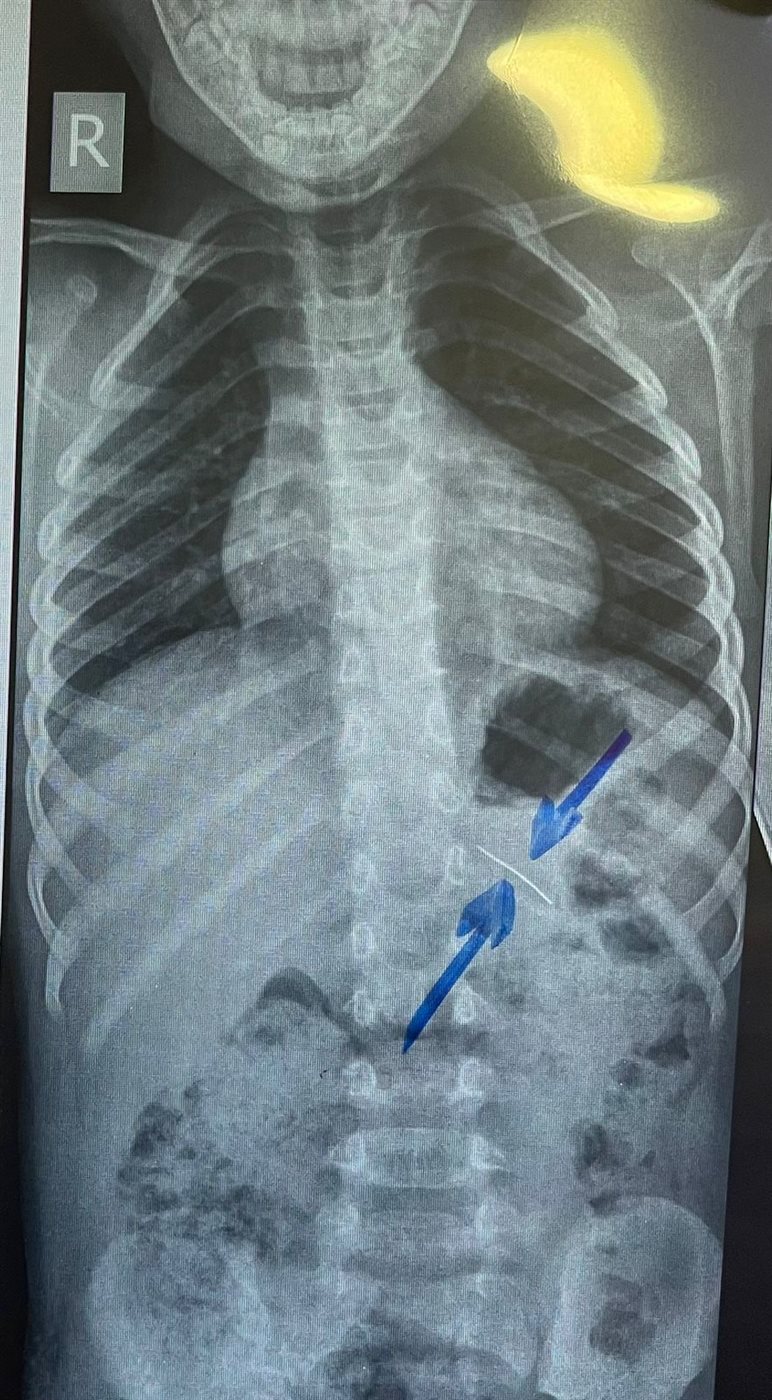

نجح فريق طبي من وحدة أمراض الجهاز الهضمي والكبد ومناظير الأطفال بقسم طب الأطفال بمستشفى سوهاج الجامعي في إجراء تدخل دقيق لاستخراج دبوس من معدة صغير يبلغ من العمر 4 سنوات، باستخدام منظار معدة خاص بالأطفال، دون حدوث أي مضاعفات، وغادر الطفل المستشفى بعد ثلاث ساعات فقط من الإجراء، وهو في حالة صحية جيدة.

وأكد الدكتور أحمد كمال، المدير التنفيذي للمستشفيات الجامعية، أن التعامل مع الحالة تم بسرعة وكفاءة، حيث تمكن الفريق الطبي من استخدام المنظار الخاص بالأطفال لاستخراج الدبوس دون أي تدخل جراحي، مما ساهم في خروج الطفل من المستشفى في نفس اليوم بحالة ممتازة.